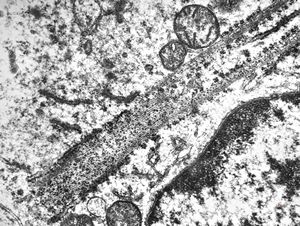

M,32y. | blood - eosinophilic leukemia